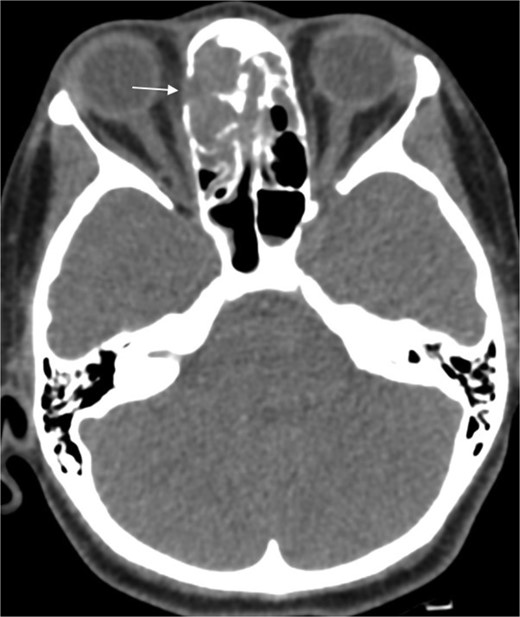

A 31-year-old man, who is a known case of Gilbert syndrome, presented to the rhinology clinic with a 1-year history of progressive bilateral nasal obstruction and left eye proptosis. The patient had previously undergone FESS twice outside the hospital for allergic fungal rhinosinusitis, with the most recent procedure having been performed two years before his presentation at the clinic. On examination, the nasal endoscopy showed extensive nasal polyposis, while the neurological examinations were normal. The CT scan and MRI revealed a mass in the left ethmoid cavity with an erosion of the lamina papyracea, extending into the extraconal fat and obstructing the frontal recess with mucosal thickening (Fig. 3). The patient was therefore suspected of having recurrent fungal rhinosinusitis and underwent FESS for debulking and to obtain a biopsy. Postoperatively, the histopathological results confirmed the diagnosis of CGIFRS, and A. flavus was found in the tissue culture. The patient was then started on oral voriconazole for 3 months.

Paranasal CT scan without contrast a mass in the left ethmoid cavity with erosion of the lamina papyracea (arrow).